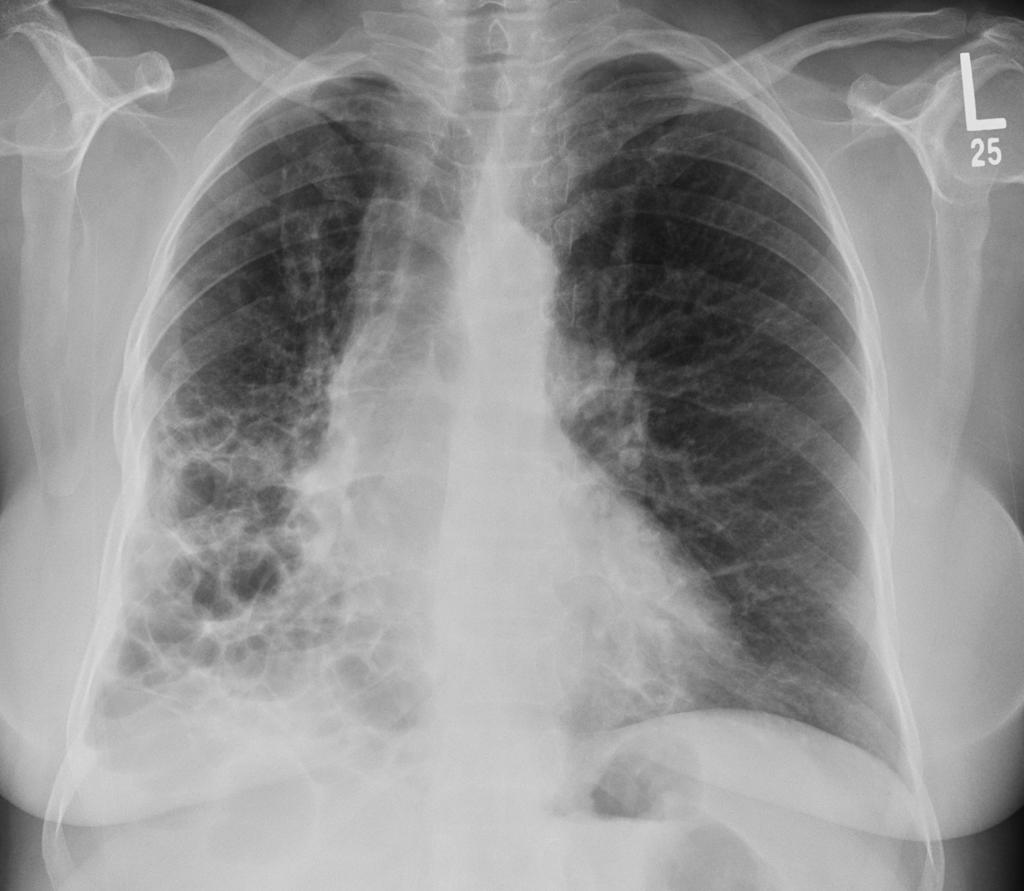

间质性肺疾病最让人头疼的症状就是呼吸困难,医学上叫"呼吸困难",患者常常形容为"像鱼离开了水"

正常人的肺就像一个高效的氧气工厂,肺泡壁薄如纸,气体交换轻松愉快

但间质性肺疾病让这个"工厂"出现了问题,肺泡壁变厚变硬,就像在氧气和血液之间加了一堵墙,气体交换效率大打折扣

美国肺脏协会的研究数据显示,间质性肺疾病患者的最大摄氧量比正常人减少40-60%

这意味着什么呢?简单说,就是别人爬三层楼不喘气,你可能爬一层楼就需要休息

这不是你娇气,而是身体的客观限制